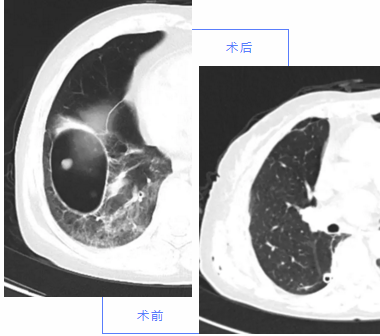

近日,我院胸外科成功完成了胸腔镜下肺包虫切除术和胸腔镜下肺癌根治术。此两例手术的成功实施,标志着我院胸外科的胸腔镜技术在持续迈向新的台阶。

肺包虫病患者

女性,68岁,反复咯血半年有余,近一个月来病情加重,前来我院胸外科就诊。胸部CT报告提示:1.右下肺含气液囊肿,考虑包虫病,建议临床进一步完善生化检查;2.右下肺间质性肺炎;3.右肺中叶纤维化病变。因患者慢性咯血,轻度贫血,上级医师查房后建议手术治疗,胸外科医师团队为其成功实施了胸腔镜下肺包虫切除术。术后患者病情平稳,目前恢复良好。